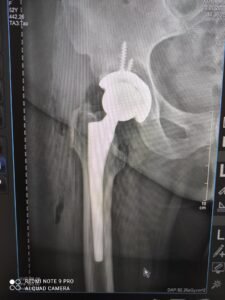

Виконували бойове завдання неподалік селища Спірне Бахмутського району Донецької області. Під час мінометного обстрілу отримав поранення гомілковостопного суглоба, який був повністю зруйнований осколками. Відвідав не один медичний заклад, думки лікарів щодо вирішення моєї проблеми були різними. З Досяком Мирославом Ігоровичем познайомився випадково через знайомих, його підхід до операції мені дуже сподобався і підходив, оскільки в Мирослава Ігоровича є великий досвід у подібних ситуаціях, особливо з військовими. Операцію проводив Мирослав Ігорович разом із Тарасом Олеговичем у Першій міській лікарні м. Львова, і вона пішла на користь, оскільки після неї я міг сміливіше ставати на ногу без тих болів, що були до операції. Хочу щиро подякувати Мирославу Ігоровичу, Тарасу Олеговичу та всьому персоналу Першої міської лікарні за їхню роботу та ставлення до мене й до інших пацієнтів лікарні, з якими я перебував там під час тривалого лікування. Щира подяка Вам!